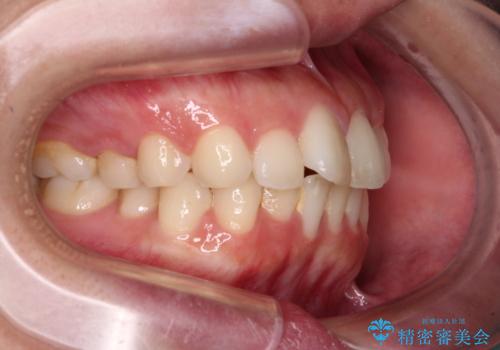

- 全体的なデコボコと口元の突出感を改善したいとのことで来院された患者様です。

このままデコボコを整えるとさらに突出感が増すため、上下左右の第一小臼歯を抜歯し、ワイヤー装置にて矯正しました。